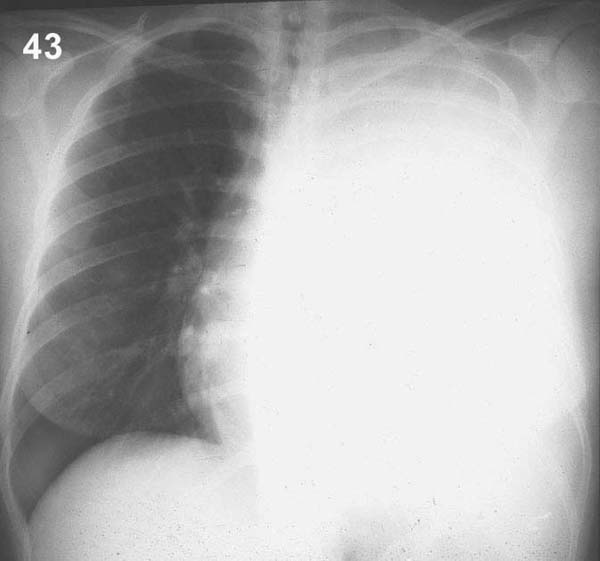

Esquema 43 Comentario placa 43 En este caso se observa un velamiento homogéneo total del hemitórax izquierdo y un desplazamiento del mediastino Y corazón hacia la derecha, todo lo cual indica un derrame pleural masivo. Pase a la placa 44. |